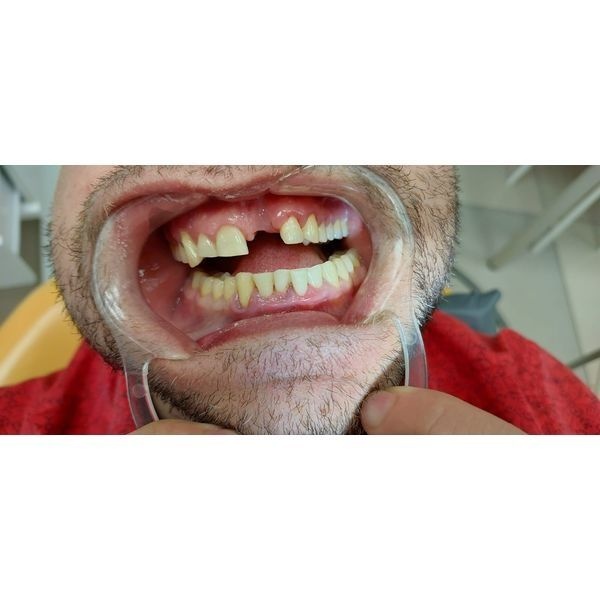

В «Центр лечения заболевания пародонта» обратился 40-летний мужчина, у которого выпал левый верхний резец (зуб 2.1).

Слизистая оболочка альвеолярных отростков обеих челюстей покрасневшая и отёчная, при зондировании кровоточила. Отмечались над- и поддесневой зубной камень тёмного цвета. Правый нижний клык и резец (зубы 1.3 и 4.1) шатались в обе стороны. Слизистая оболочка в области выпавшего зуба сформирована двумя слоями.